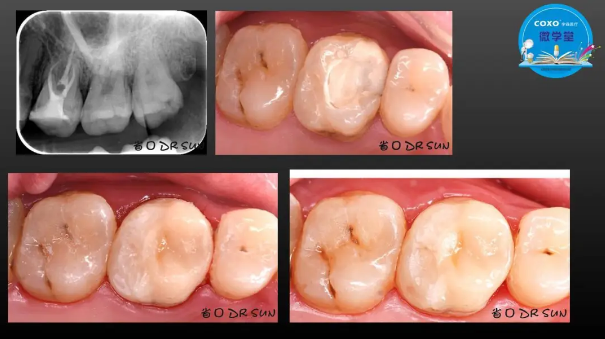

主講:孫書昱

主任醫(yī)師,牙體牙髓副主任, 廣東省口腔醫(yī)院牙體牙髓科 主任醫(yī)師。2003年碩士研究生畢業(yè),研究方向為牙體牙髓病學,擅長于牙體牙髓病的診斷、齲齒、牙髓炎、根尖周病的治療以及前牙美容修復。